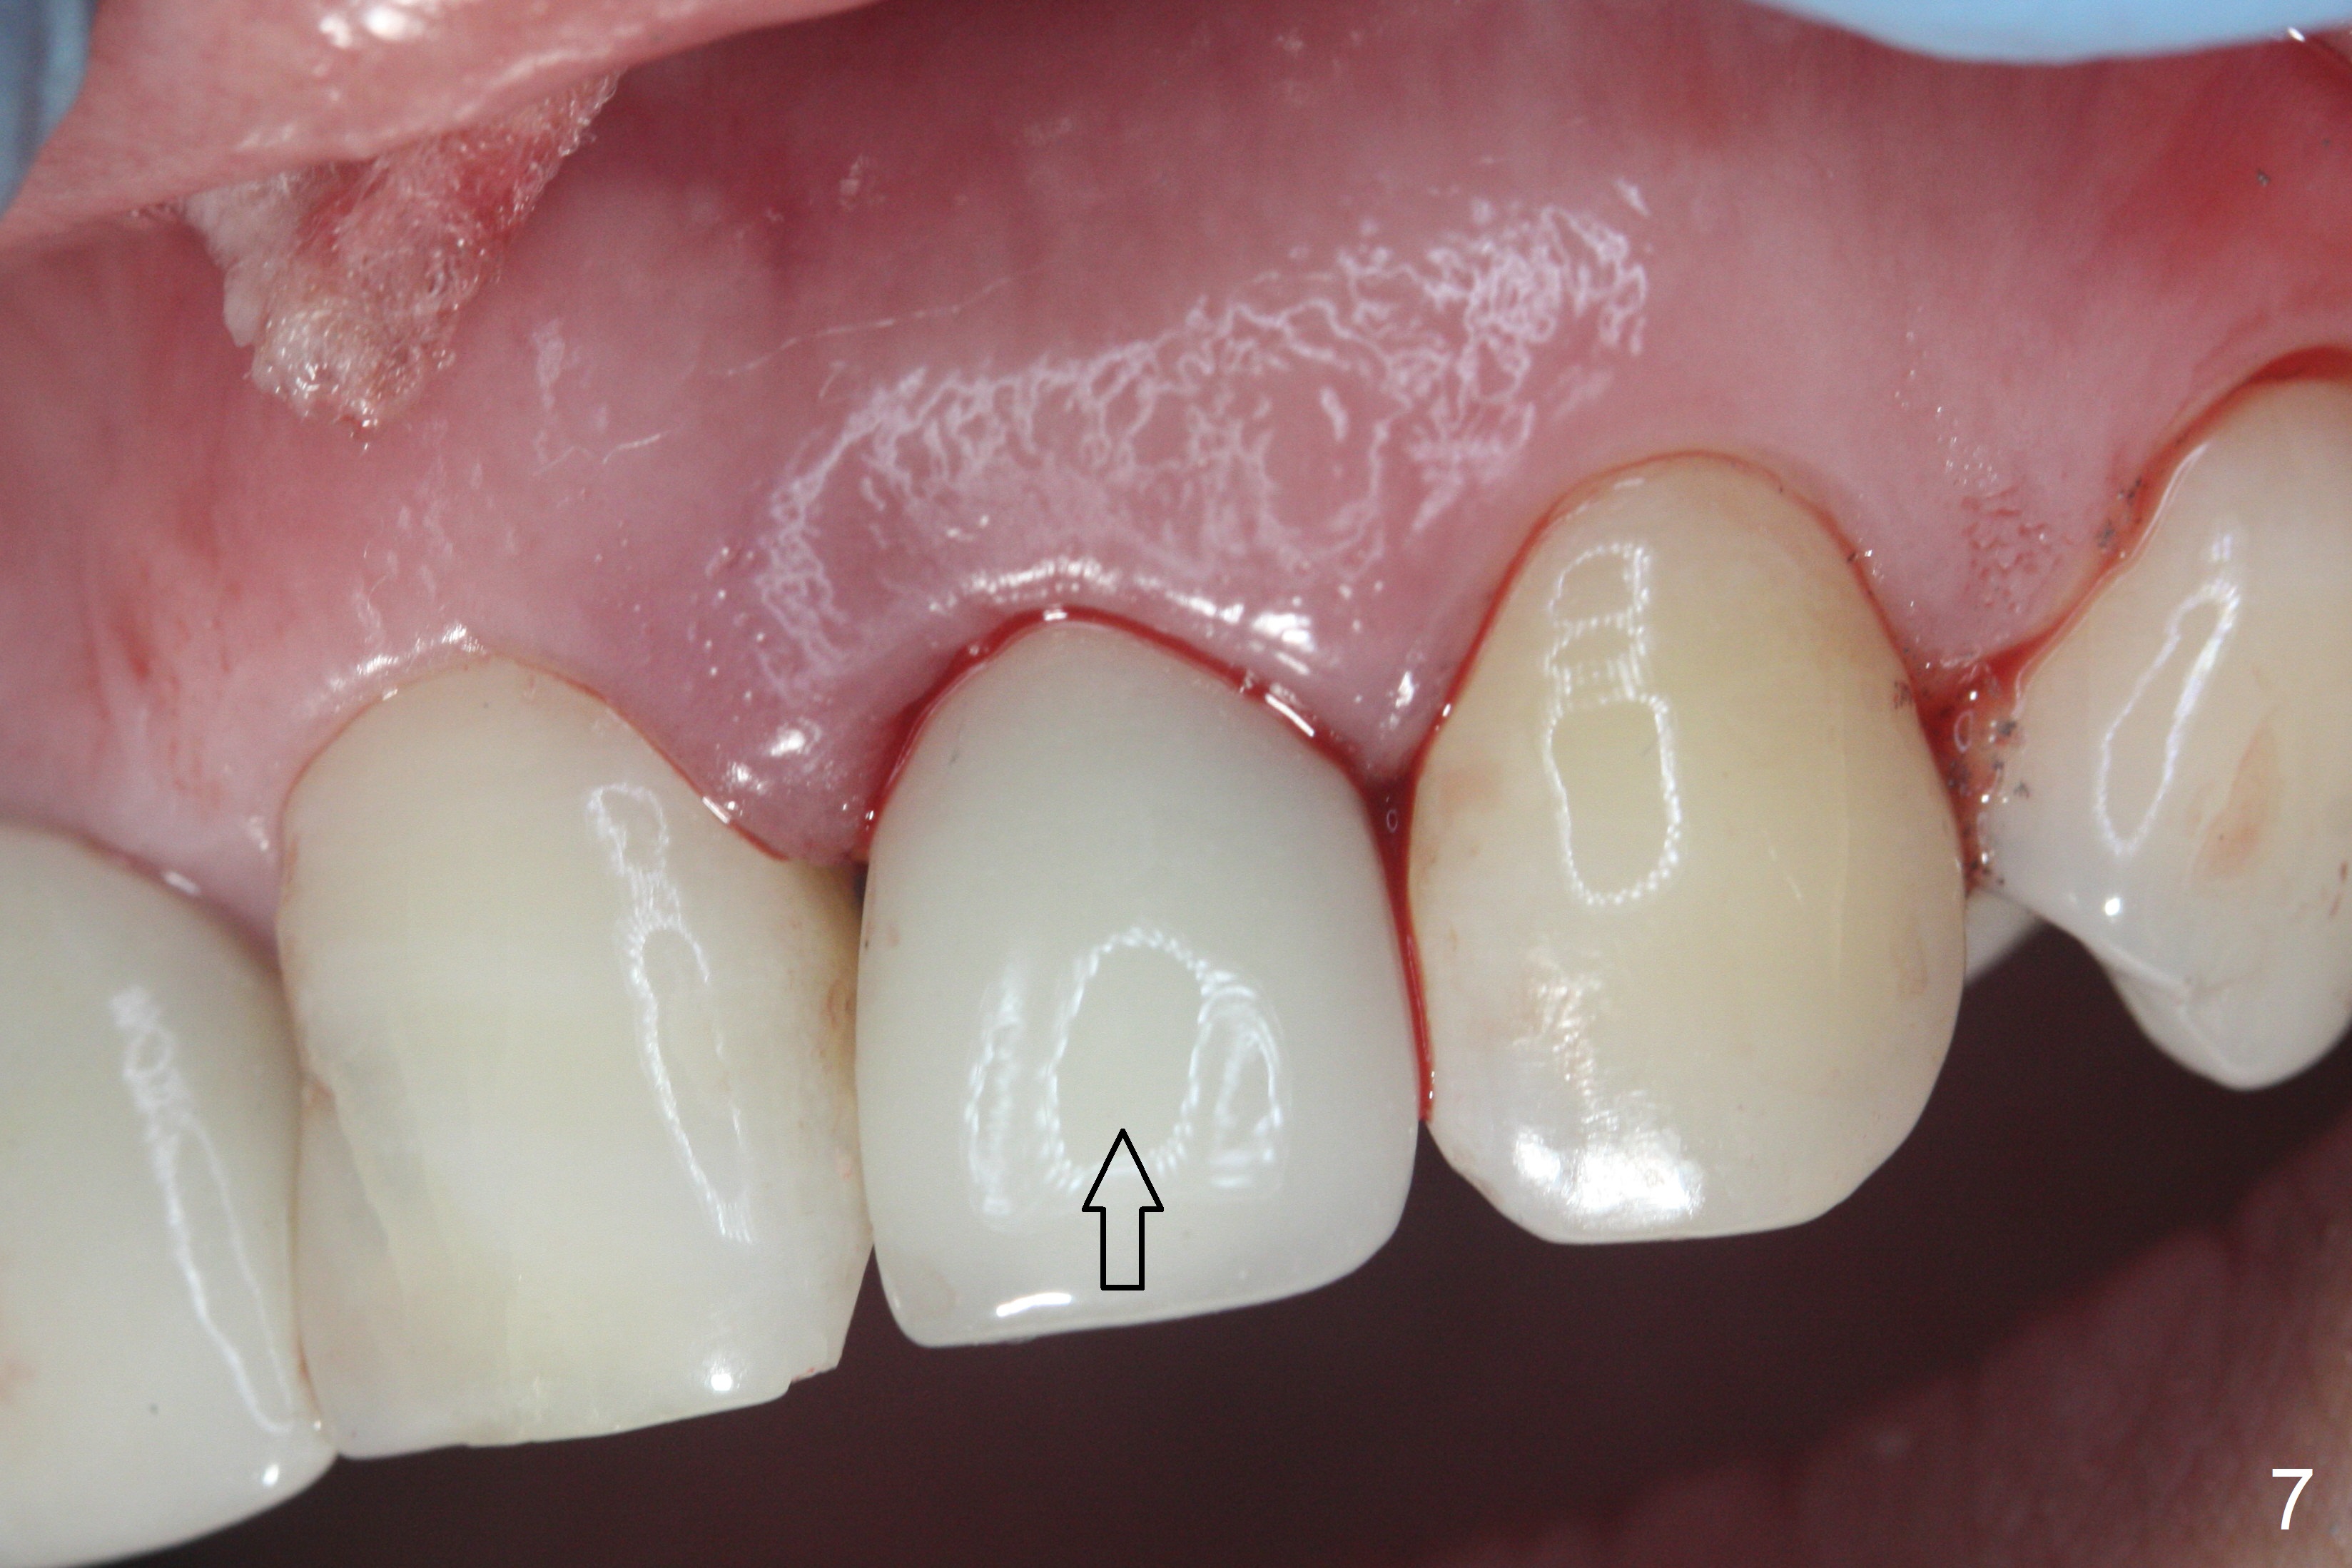

When the patient returns, the crown at #10 has displaced incisally (Fig.1,2 arrow). The initial depth is 15 mm (Fig.3, palatal gingival margin). After a 3.8x12 mm SM implant is placed (Fig.4), allograft is packed in the peri-implant space (*, as compared to Fig.3) and a 3.9x4(3) mm abutment is placed (A). More allograft is placed in the peri-abutment space (Fig.6 *). The existing crown (Fig.4,5 C) is hollowed, relined (R) and used as an immediate provisional (Fig.7-9). The patient is pleased with the appearance of the apically-repositioned provisional (Fig.7 arrow). She returns for impression 3.5 months postop (Fig.10). After change of abutment to 3.9x4(4.5) mm and new provisional, impression is retaken 5 months postop (Fig.11,12). It appears that the implant is palatally placed and a little large for the site (Fig.11 (B: buccal); Fig.12 (^: thin layer of the palatal plate)). If an angled abutment were used, a screw-retained crown might have been feasible. Due to the new provisional, the gingiva looks healthy when a permanent crown is cemented (Fig.13).